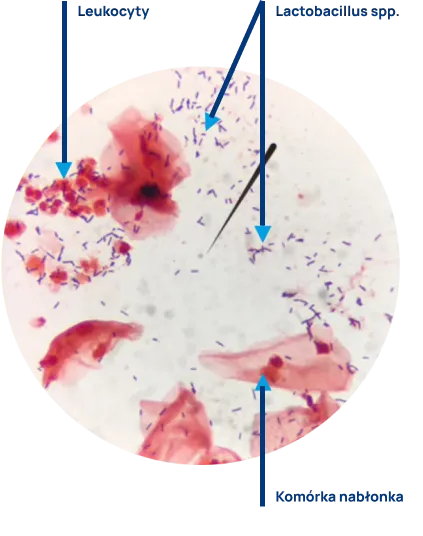

Ocena preparatu mikroskopowego obejmuje opis liczebności pałeczek kwasu mlekowego, pozostałych bakterii, grzybów, nabłonków i leukocytów. Prawidłowy wynik badania (liczne pałeczki Lactobacillus spp., brak lub skąpa liczba pozostałych bakterii, brak leukocytów, brak grzybów) wskazuje na równowagę drobnoustrojów w pochwie. Nieprawidłowy wynik badania (zaburzenie biocenozy pochwy) nasuwa podejrzenie zakażenia i jest wskazaniem do dalszej diagnostyki i podjęcia leczenia.

Fot. Aleksandra Johaniuk Pracownia Mikrobiologii ALAB laboratoria Sp. z o. o. Szczecin